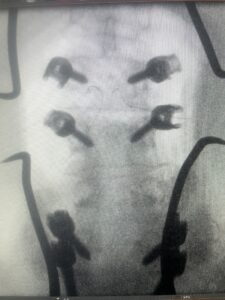

This 61-year-old female with a history of severe osteoporosis and a prior history of a laminectomy from l2-S1 with an L5-S1 instrumented fusion, presents with progressive low back pain and right lower extremity radiculopathy. MRI revealed a grade 1 L2-3 spondylolisthesis with severe stenosis mainly from severe right L2-3 facet joint hypertrophy which was compressing the right L3 descending nerve root. (Fig. 1). She had failed conservative management consisting of physical therapy and pain management with epidurals. She underwent an L1-3 revision laminectomy where we had to dissect a plane underneath the inferior aspect of the L2 lamina. We performed an instrumented fusion at L2-3 with special hydroxyapatite-coated screws to improve fixation to surrounding bone given here severe osteoporosis (Fig. 2) This worked out well and the patient had an uneventful recovery with relief of her leg pain.

Figures 1a: Sagittal and axial T2-weighted lumbar MRIs demonstrating a grade 1 L2-3 spondylolisthesis (red arrow) with severe stenosis secondary to right L2-3 facet hypertrophy (red arrow).

Fig 1b: Note the left L2-3 facet joint (blue arrow) is normal in size compared to the right (red arrow)

Fig: 2a: AP and lateral intraoperative fluoroscopic images demonstrating good placement of L2-3 pedicle screws